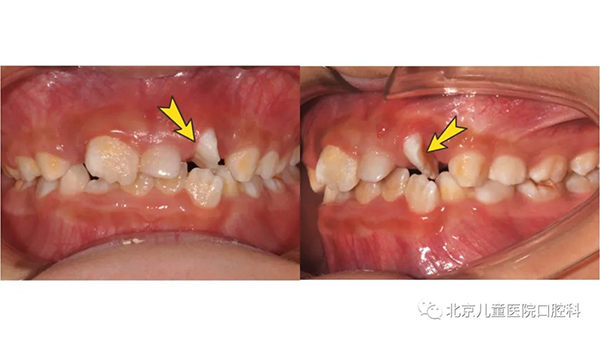

同时,在这个阶段孩子的乳牙逐渐替换为恒牙,有的时候周围的牙都替换了,却只有一颗牙迟迟不松动;有的时候乳牙脱落了很久,新牙还没有长出来;或者新牙长出来却是“扭着身子”的……这有可能是存在多生牙、融合牙、牙齿异位萌出、牙扭转等问题。

这些“隐性”问题可能无法自行发现,建议孩子6至7岁到口腔科就诊进行系统的口腔检查,需要时及时治疗,以免造成更严重的影响。

上颌六龄齿卡在前面乳磨牙颈部,位置低,长不出来(上图),六龄齿位置较为隐蔽,萌出时不替换乳牙,萌出障碍很难发现(下图)